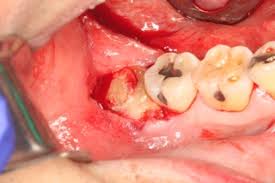

Empty looking socket with bone exposed

• Empty-looking (dry) socket as no blood clot noted

• Visible bone in the tooth socket